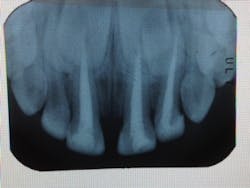

For those of us who treat baby bottle syndrome / early childhood caries (BBS/ECC), saving or restoring the beautiful smile of a toddler or pre-schooler (we’ve treated children as young as 14 months) can be quite challenging. Often, the primary anterior teeth are decayed to the point that there is little tooth structure left and the decay is deep, exposing the pulp or leaving it severely compromised.

Full pulpectomy (what the CDT code calls “Pulp Therapy”) is often indicated as indirect pulp caps (IPC) or pulpotomies may lead to abscesses and loss of the tooth.

With anterior primary teeth, if the decay is deeper than “superficial,” pulpectomy may be indicated. In my experience, IPC’s and pulpotomies in those teeth often lead to abscesses and more failures.

To remove the vital, but hyperemic pulp, place 3 fine/x-fine broaches down the canal and slowly “twirl” them around each other. By doing that, the pulp will be intertwined onto the broaches and can be removed, often in one piece. Gentle filing with a #40 Hedstrom or Fine-Cut file (NEVER longer than 16mm) will remove remaining pulp remnants. It is NOT necessary, nor advisable to irrigate with bleach. I use local anesthetic solution to irrigate, then dry with paper points, disinfect and control hemostasis with your medicament of choice on a paper point, and fill with a resorbable, NON-HARDENING paste. I use Vita-Pex, an iodoform / calcium hydroxide formulation that does not harden, and will resorb with the tooth. Pastes that harden, like ZOE, often will not resorb as quickly as the tooth, and can deflect the path of eruption of the permanent tooth.

After filling the root canal, carefully remove the Vita-Pex from the pulp chamber with a caries excavator, down to the level of the gingiva, so as not to stain the crown of the tooth (Vita-Pex has a yellowish color and will “shine through”), and also to leave room for a Resin Modified Glass Ionomer (RMGI) to be placed in the tooth chamber to seal the canal. The RMGI can even be extruded past the chamber to act as a core for the composite crown that will be built on the tooth, as described in “Strip Crown Success.”